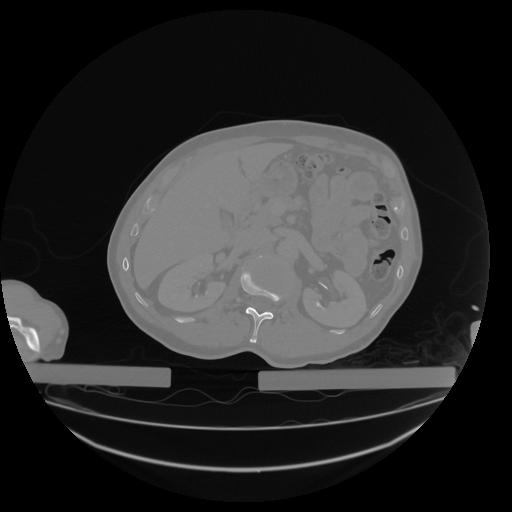

34 CUERPO,CE,Vol,1.0,CUERPO,,